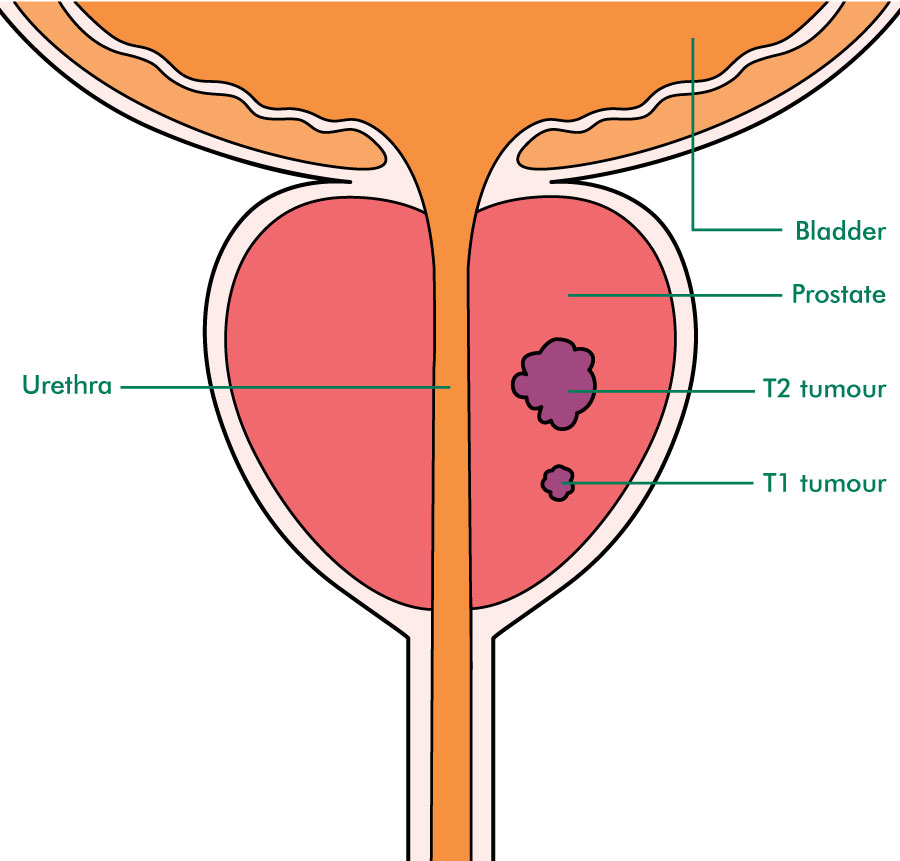

Prostate Cancer Stages – University Health News

Staging and grading | Early prostate cancer – Macmillan Cancer Support